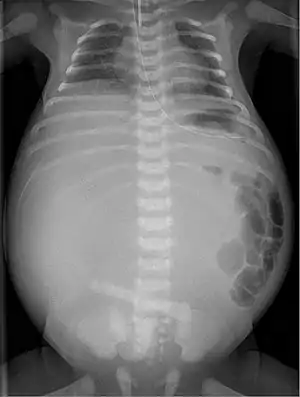

In terms of the clinical presentation often it is abdominal distension (at birth)[1]

Twenty percent of infants born with meconium peritonitis will have vomiting and dilated bowels on x-rays which necessitates surgery.